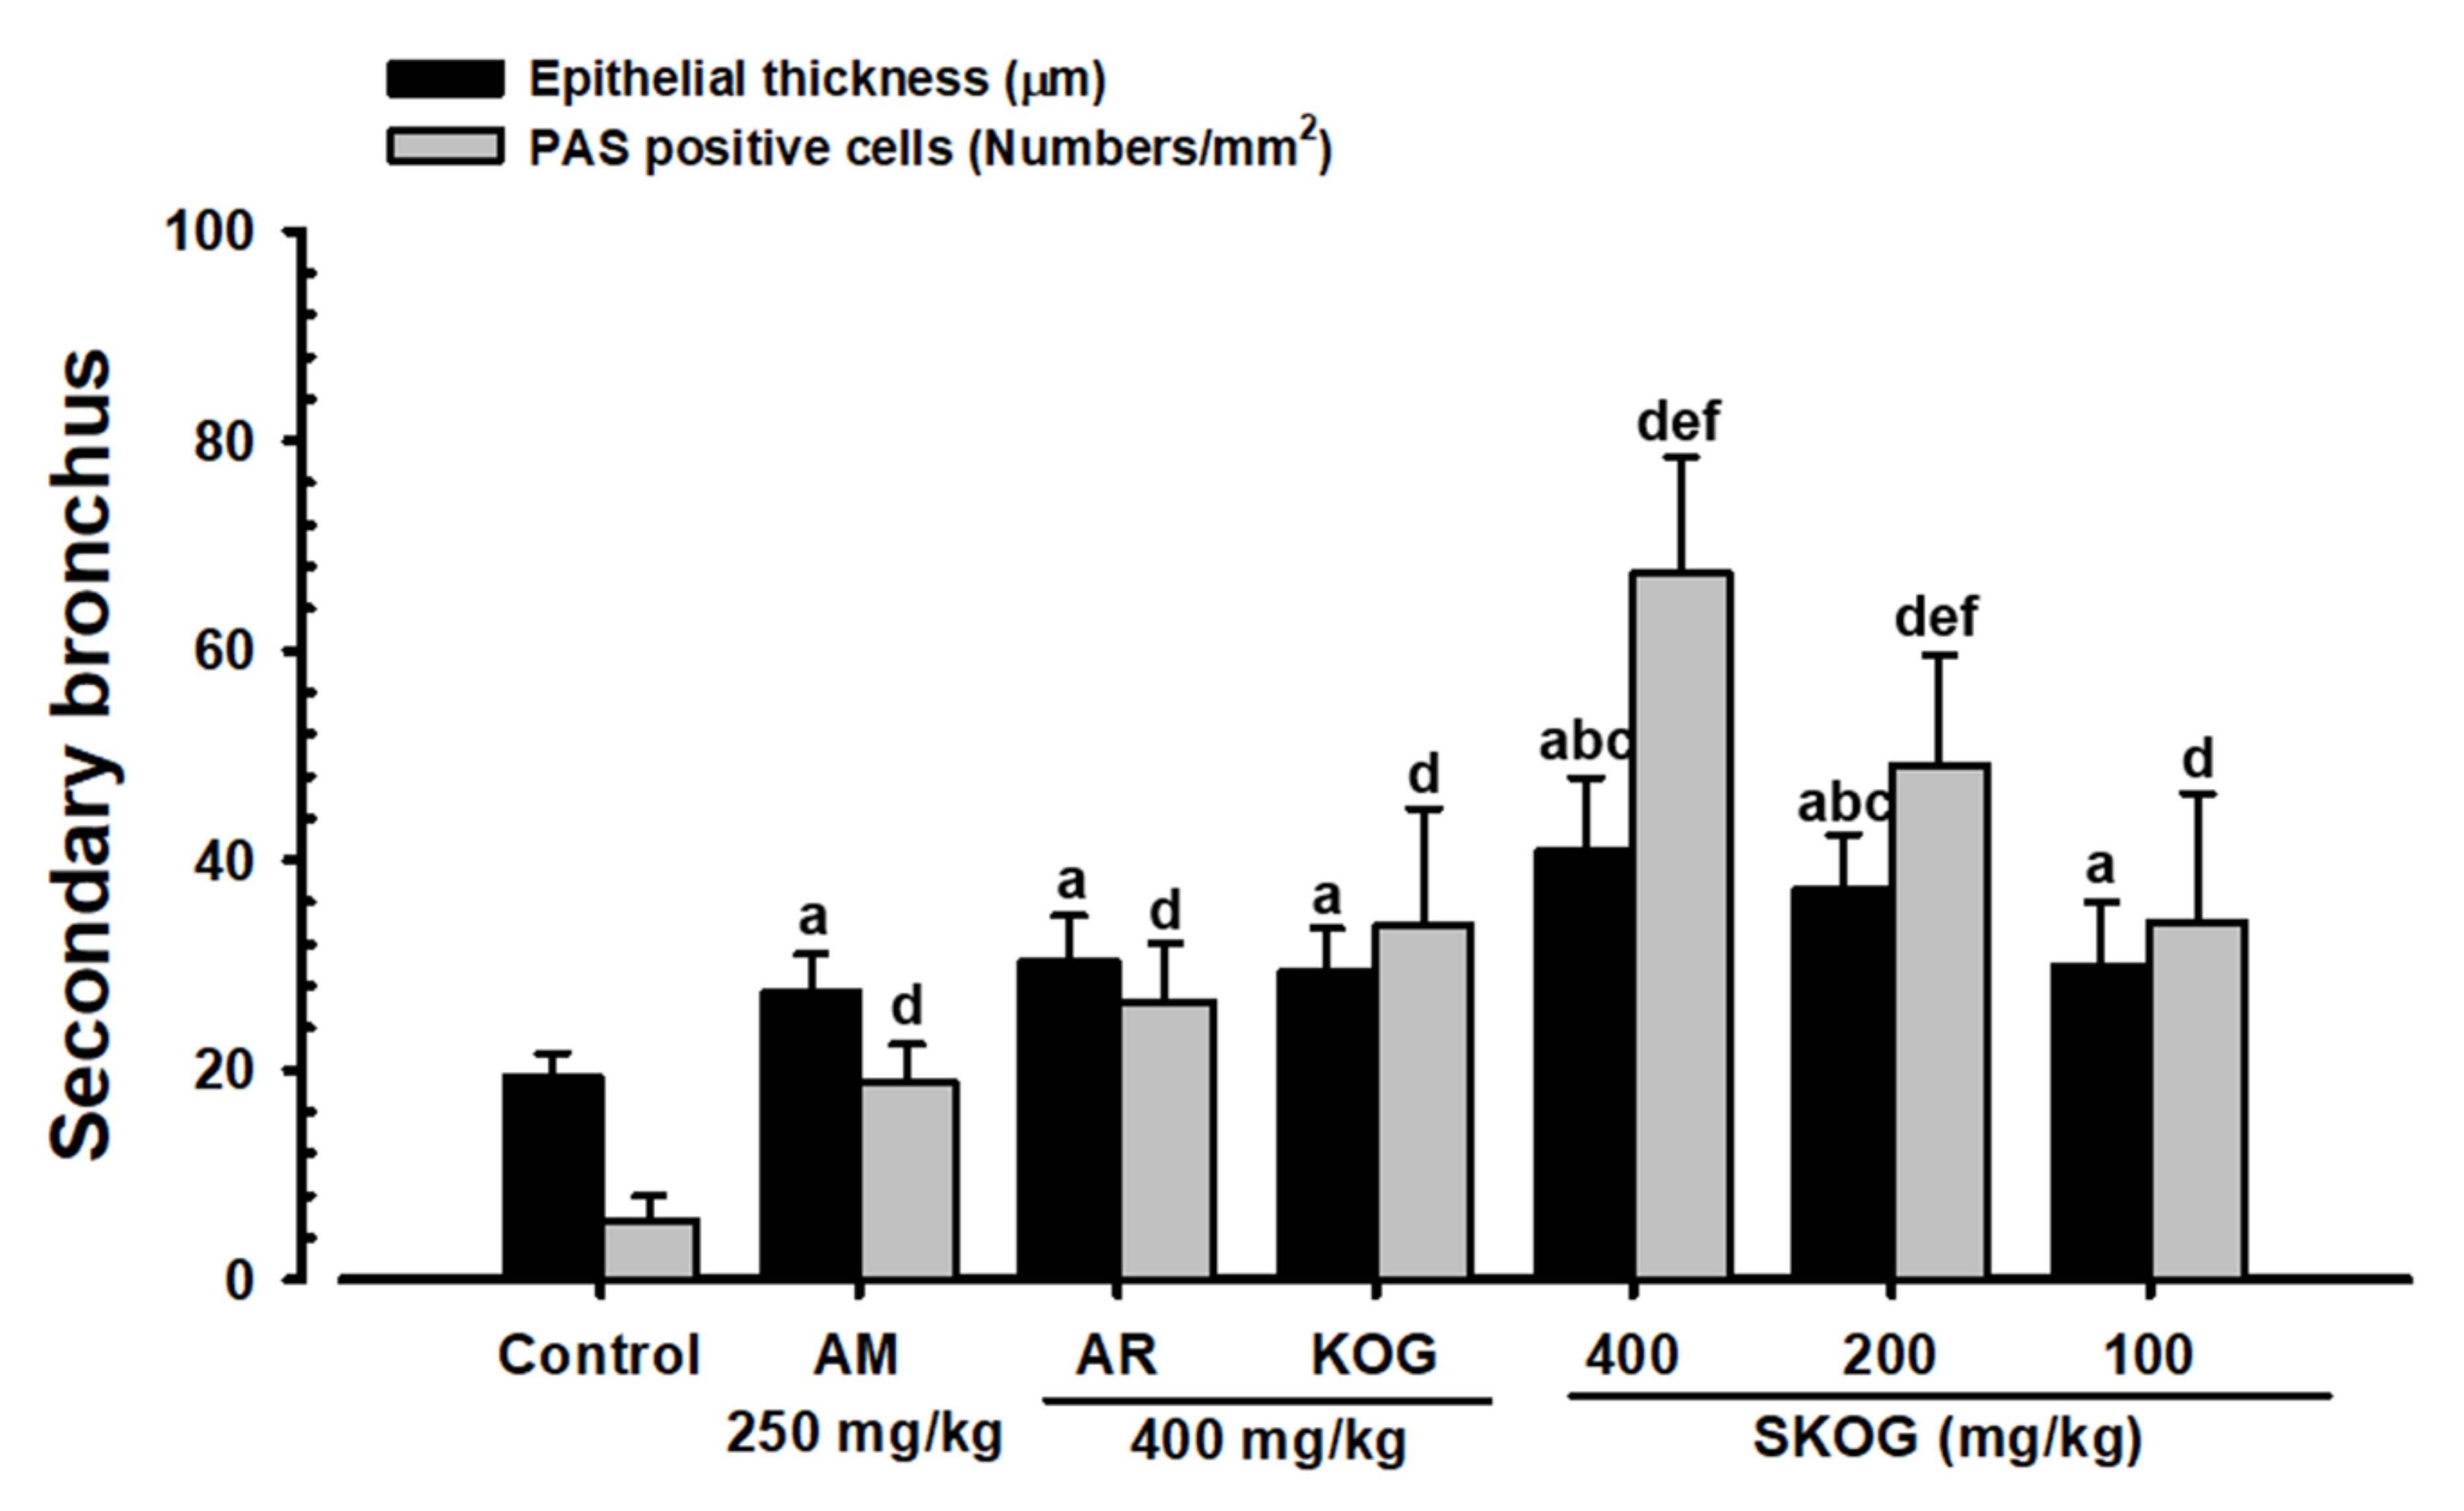

3.3.4. Histopathological Findings in the Intrapulmonary Secondary Bronchus

3.4. Anti-Inflammatory Assay